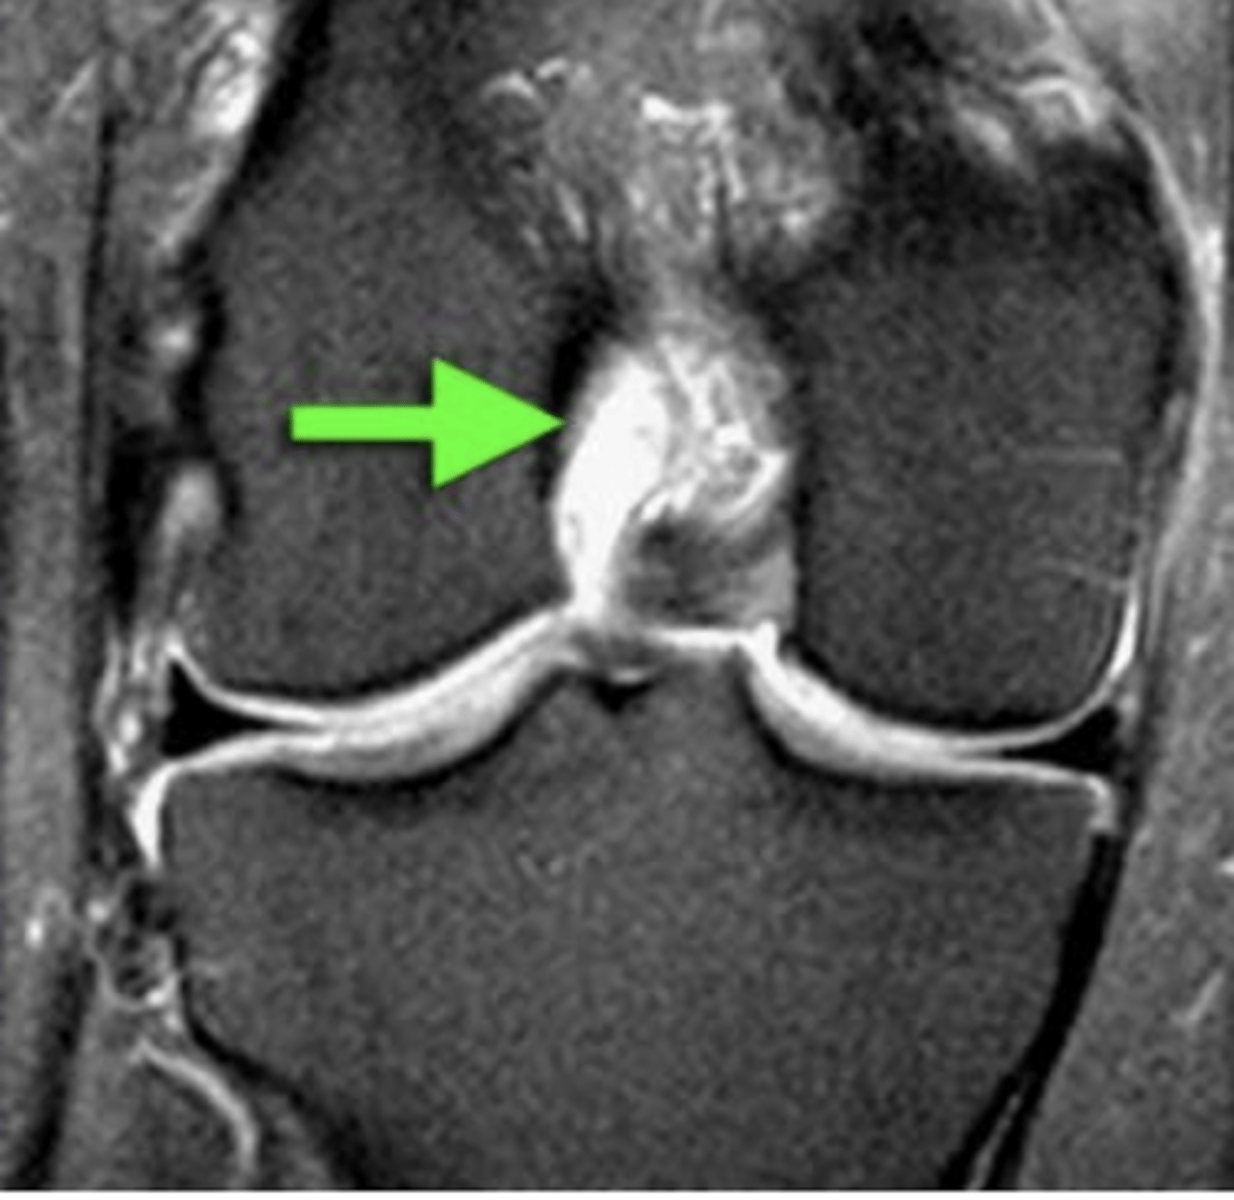

Complete tear of the ACL (right down the middle)

Define the pathology.

Complete tear of the ACL